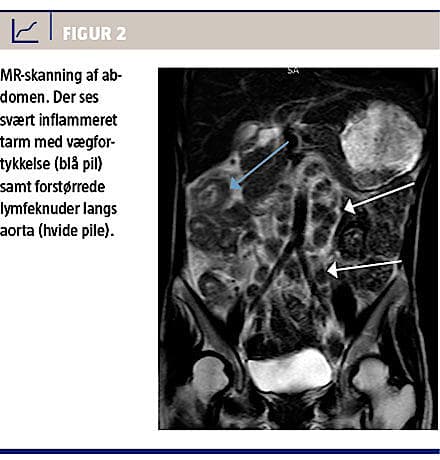

Koloskopien viste nekrotiske områder med cobblestone-tegning i transversum frem til højre fleksur, hvor man ikke kunne komme videre frem pga. forandringerne (Figur 1). En MR-skanning viste flere steder fortykkelse af tarmvæggen, betydeligt ødem ileocøkalt og forstørrede glandler paraaortalt og langs iliacakarrene (Figur 2).

We describe a case of intestinal tuberculosis in a 34-year-old Indonesian woman. She presented with diarrhoea, weight loss, fever and night sweat over a period of weeks. She underwent colonoscopy which showed a major cobblestone pattern like necrosis in part of the colon. An MR scan showed oedema involving the small intestine near the ileocoecal area and abdominal lymphadenopathy. Because of the patient history of recent TB exposure, ethnicity and positive T-SPOT-TB, she was given a course of four-drug tuberculosis treatment and responded quickly. Later on Mycobacterium tuberculosis was found in faeces culture.